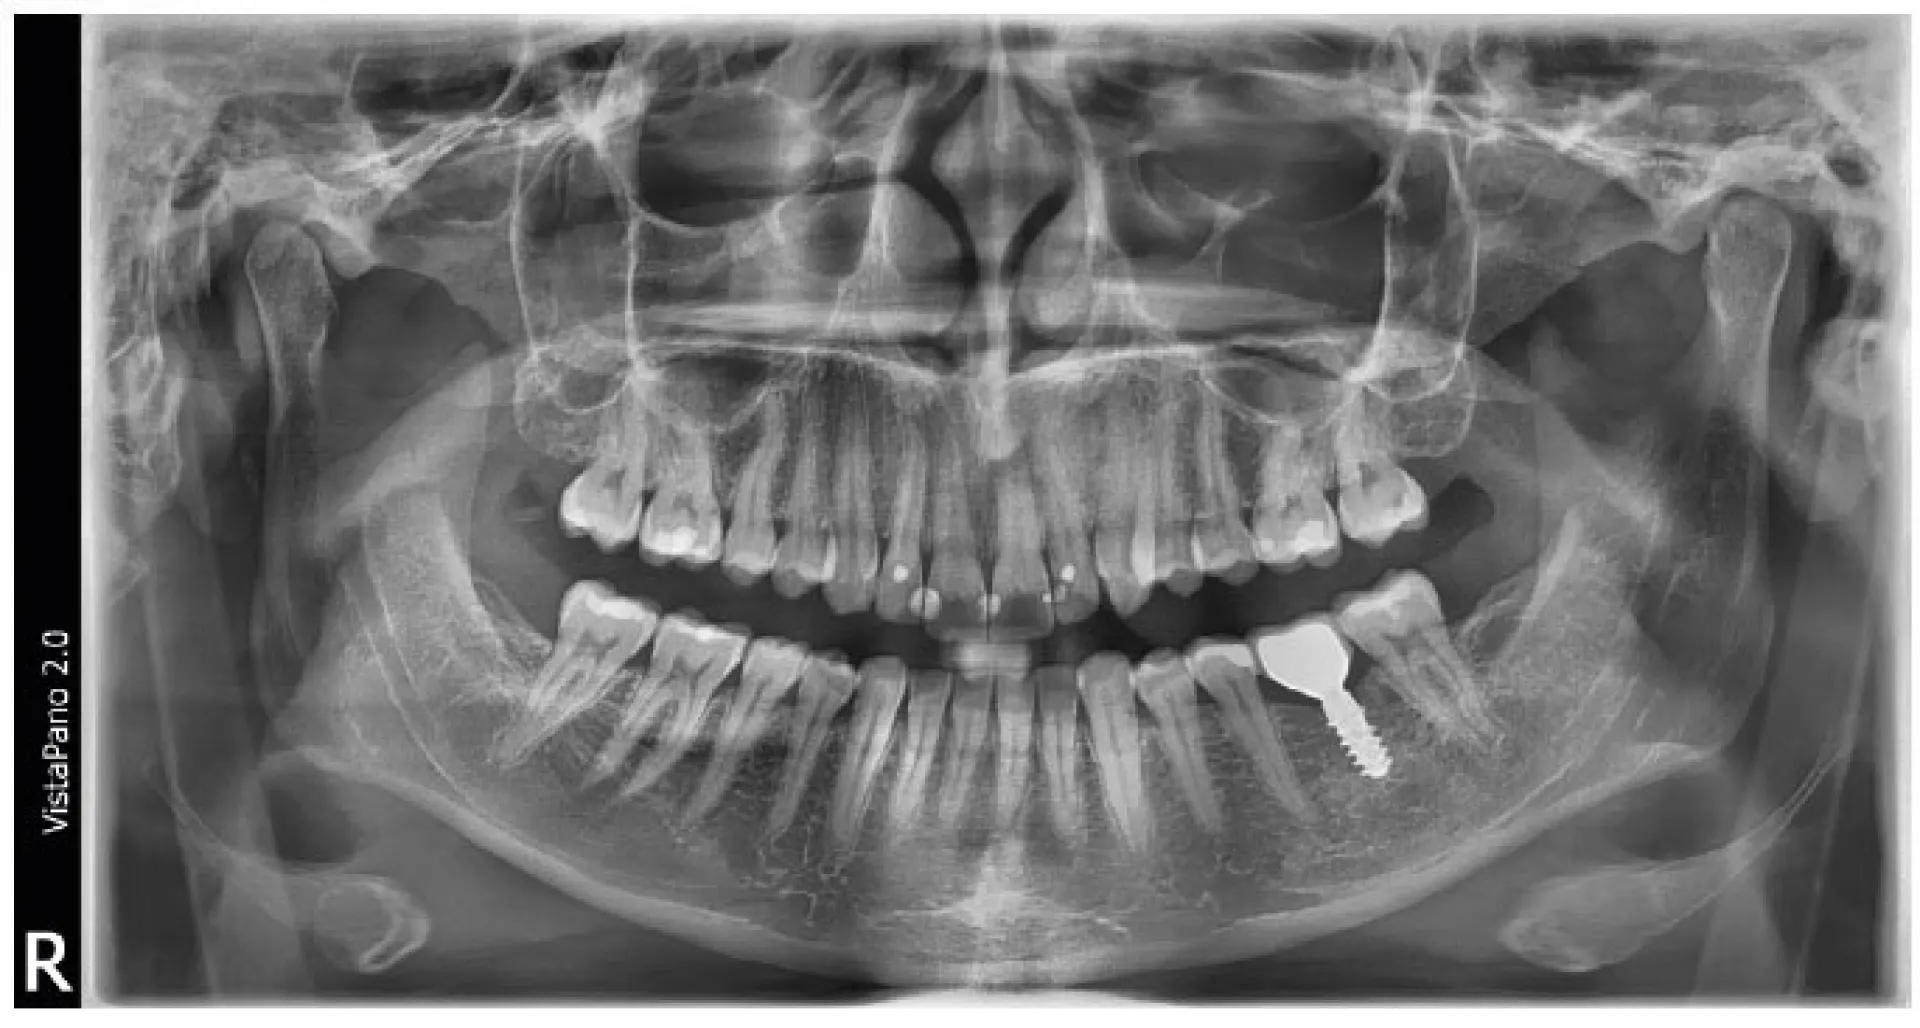

Avec le VistaPano S 2.0, Durr Dental définit une nouvelle norme en termes de netteté d’image des clichés extra-oraux. Par ailleurs, l’appareil de radiographie panoramique 2D s’illustre par une utilisation simple et un flux de travail bien pensé, assisté par un écran tactile en verre 8" innovant. Le VistaPano S 2.0 offre un rendu exceptionnel, et ce grâce aux deux technologies innovantes qu’il intègre. D'une part, la technologie de capteur CsI innovante garantit une qualité d'image accrue permettant ainsi d'établir de meilleurs diagnostics. D'autre part, la technologie S-Pan exploite les données d'image du cliché individuel du patient pour montrer automatiquement une représentation panoramique parfaitement nette, et ce à chaque position spatiale de la mâchoire et des dents.

Contrairement à la méthode traditionnelle, la technologie S-Pan sélectionne automatiquement, parmi de nombreuses couches parallèles, les sections d’image qui représentent le mieux l’anatomie individuelle du patient. Lors de l’assemblage de l’image panoramique, les écarts par rapport à la « dentition moyenne » sont également pris en compte, tout comme l’inclinaison individuelle des dents. On obtient, par conséquent, une image d’une clarté exceptionnelle qui permet au dentiste de trouver immédiatement les structures pertinentes. Comme la reconstruction s'oriente en fonction de la situation effective de la dentition, les erreurs de positionnement sont « compensées » dans certaines limites. Ainsi, le cabinet gagne du temps, et le client ne subit aucune répétition de clichés.